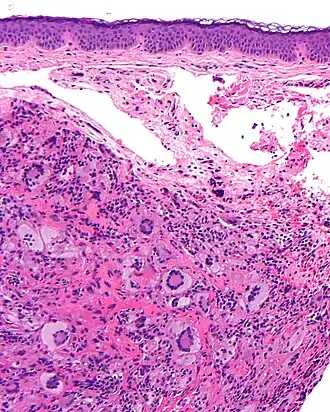

La coupe histologique (grossissement : × 40) montre un infiltrat dermique (dense et bien limité) composé d'histiocytes, de cellules géantes de Touton, et parfois de cellules mastocytaires, et d’un infiltrat inflammatoire lymphocytaire (lymphocytes, éosinophiles, neutrophiles).

L'infiltration affecte le derme papillaire et parfois réticulaire ou le niveau des tissus sous-cutanés, du fascia et des muscles.

Le derme peut être très aminci par l'infiltrat et alors s'ulcérer.

Les xanthogranulomes contiennent dans un premier temps des histiocytes non lipidiques, sans cellules de langerhans. Ensuite, des cellules inflammatoires (dont des histiocytes spumeux) apparaissent, de plus en plus nombreuses avec la maturation de la tumeur. Des cellules géantes de Touton aux noyaux arrangés en couronne, sont typiques, avec parfois d'autres cellules géantes, « endothéliales »[20].